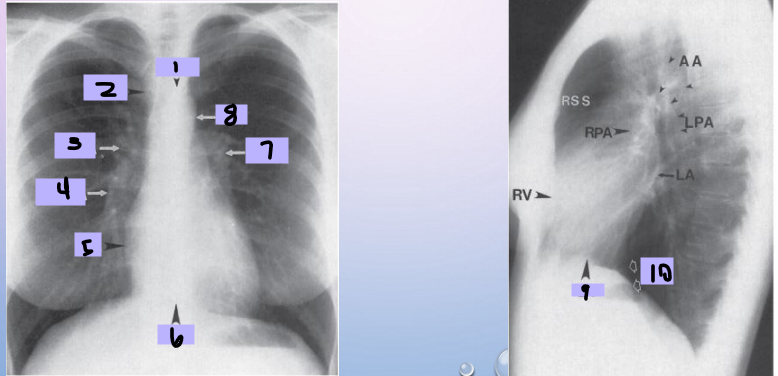

Aortic arch

#1

Superior vena cava

#2

Right pulmonary artery

#3

Right descending pulmonary artery

#4

Right atrium

#5

Right ventricle

#6

Left pulmonary artery

#7

Descending aorta

#8

Left ventricle

#9

Inferior vena cava

#10